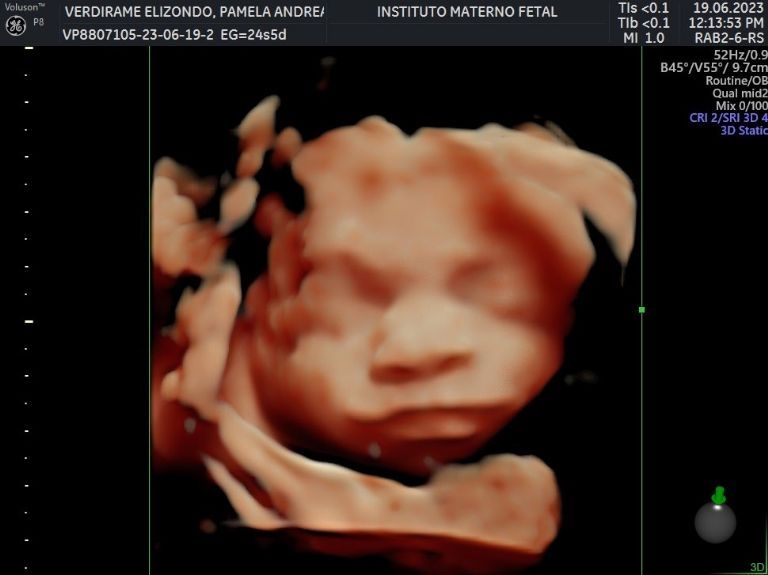

Hace apenas unos días, la pareja de atletas compartió por primera vez algunas imágenes de su ultrasonido, mismas en las que se puede apreciar que el bebé ya se encuentra perfectamente formado e incluso se distinguen algunos de sus rasgos, por lo que hubo quienes trataron de buscarle parecido y fue tal el furor que causaron que superaron las 27 mil reacciones, además de que se llevaron cientos de felicitaciones.

Actualmente, Pame tiene 26 semanas de gestación, de tal forma que ya llevaba más de la mitad del proceso. De acuerdo a lo que ha compartido, el bebé podría nacer a principios de octubre, así que falta poco para que lo puedan tener entre sus brazos, mientras tanto se encuentran comprándole algunas cositas y preparan la decoración de su habitación, pues quieren que todo se encuentre perfecto para recibir a su pequeño.